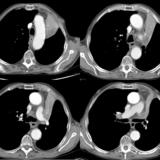

LUL Collapse Case 1 CT 4in1

Date: 02/19/2004

Views: 3518